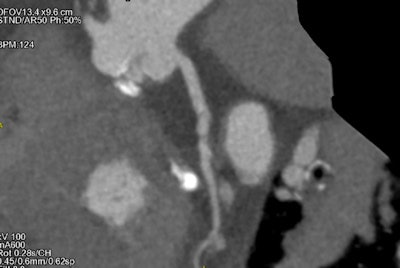

The researchers conducted axial prospective assessment (cardiac cycle phases 40% to 80%). ECG-gated scanning was utilized to examine the thorax, and spiral non-ECG-gated scanning of the abdomen immediately followed. The contrast flow was 5 mL per second, followed by 50 mL physiological solution and use of iterative reconstruction (adaptive statistical iterative reconstruction, ASIR-V at 50%). Two experienced radiologists and one resident radiologist performed the analysis.

The average volume of contrast media was 55 ± 8 mL, while the average attenuation of all vessels was greater than 350 HU.

The evaluation of the peripheral access vessels and dimensions of the ascending aorta, aortic root, and aortic annulus (when requested) were performed in all patients. The mean cardiac frequency was 74.18 ± 12.32 bpm, and the presence of atrial fibrillation in six patients did not affect the diagnostic performance, Fiore and colleagues noted.

Dose length product was 532.3 ± 200.0 mGy-cm, and CT dose index for the axial acquisition was 13.87 ± 6.92 mGy and for the helical 3.85 ± 1.35 mGy.